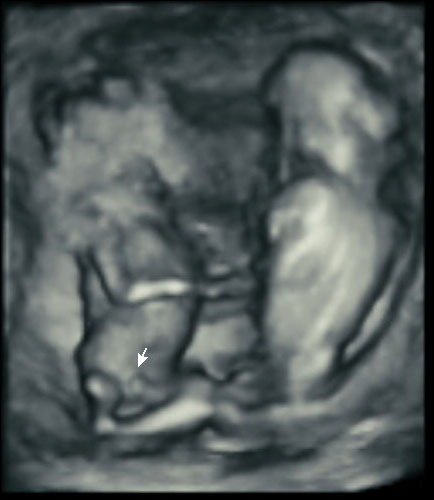

Here’s how ultrasound works in pregnancy: As early as 16 weeks, women can see a “fetal portrait” of their baby and determine its gender. Ultrasound technology has improved dramatically over the decades from flat, grainy black and white images to the current three-dimensional time experience.

Most hospitals offer some 3D scanning, but 3D ultrasound produces images that show the width, height and depth of a developing child. Rather than sending sound waves straight into the womb and recording when they bounce back as is common in 2D imaging, 3D ultrasound sends sound waves from different angles. A computer then renders a 3D image based on this data.

4D ultrasound adds movement as it occurs. The fourth dimension is time. You’re actually watching your baby live in 3D mode. How cool is that?